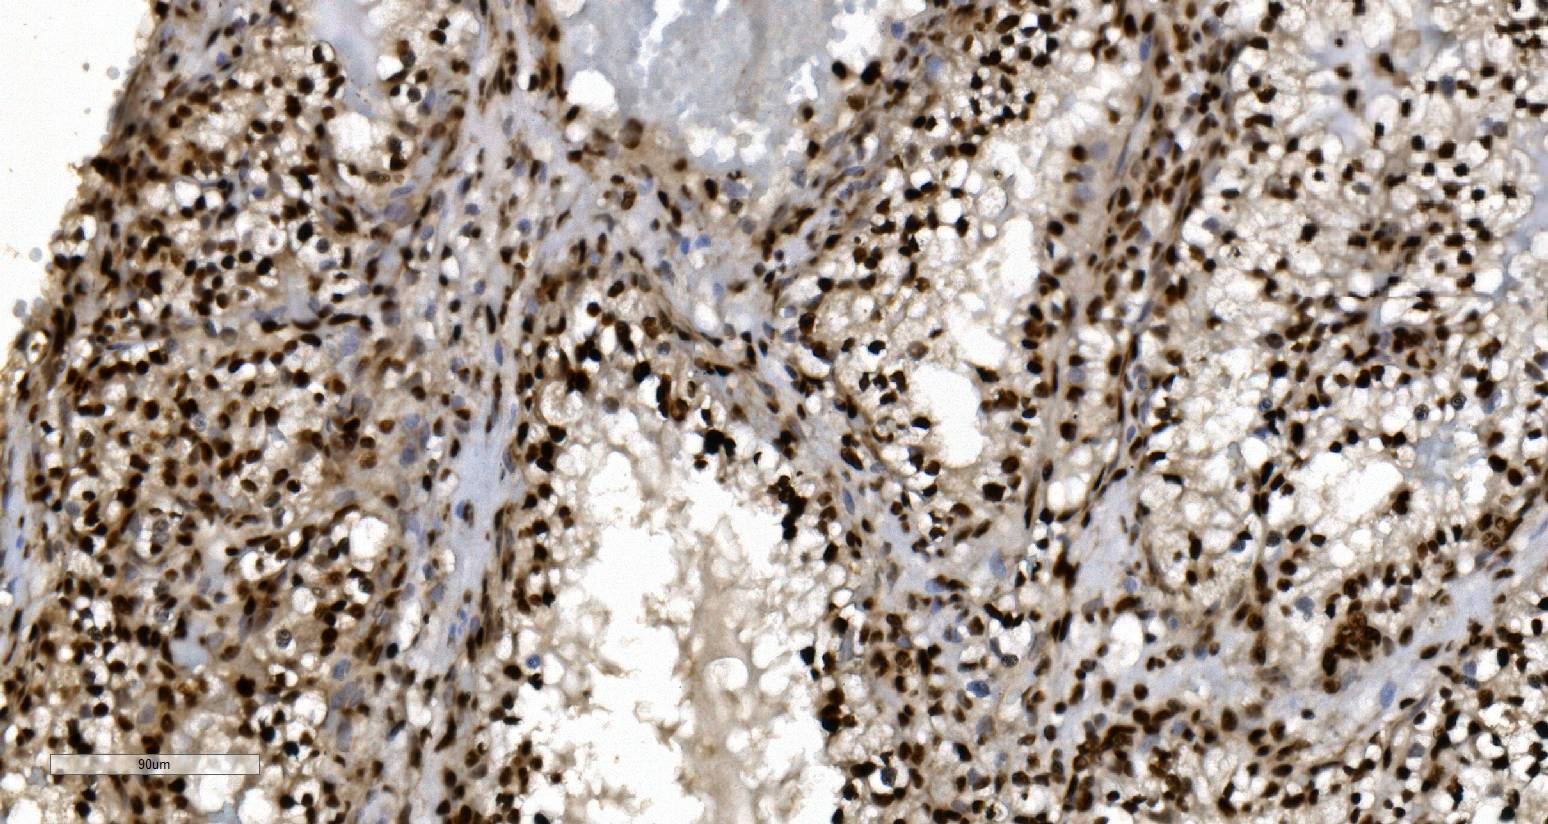

IHC analysis of KU70/XRCC6 using anti-KU70/XRCC6 antibody (M01732-4).

KU70/XRCC6 was detected in a paraffin-embedded section of human gallbladder adenocarcinoma tissue. Biotinylated goat anti-mouse IgG was used as secondary antibody. The tissue section was incubated with mouse anti-KU70/XRCC6 Antibody (M01732-4) at a dilution of 1:200 and developed using Strepavidin-Biotin-Complex (SABC) (Catalog # SA1021) with DAB (Catalog # AR1027) as the chromogen.